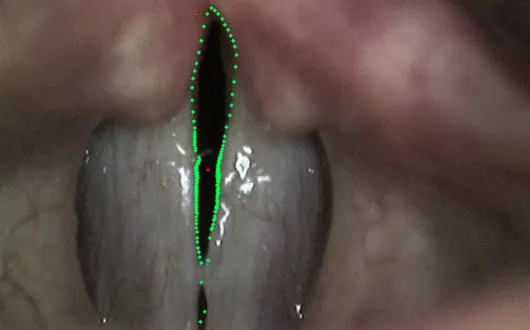

Głos jest podstawowym sposobem komunikacji międzyludzkiej i ma szczególne znaczenie w takich zawodach jak nauczyciel, dziennikarz czy pracownik centrum konferencyjnego. Wczesna diagnostyka zawodowych zaburzeń głosu staje się jednym z priorytetów zdrowia. Obecnie standardy europejskie podkreślają konieczność kompleksowej oceny zaburzeń głosu, dokonywanej podczas badania laryngologicznego lub foniatrycznego. W ostatnich latach rozwinęły się techniki rejestracji obrazów laryngoskopowych w tym sekwencji obrazów drgań fonacyjnych fałdów głosowych. Rozwijane są również skuteczne metody komputerowej analizy takich obrazów. Techniki te przyczyniają się do obiektywizacji diagnostyki foniatrycznej.